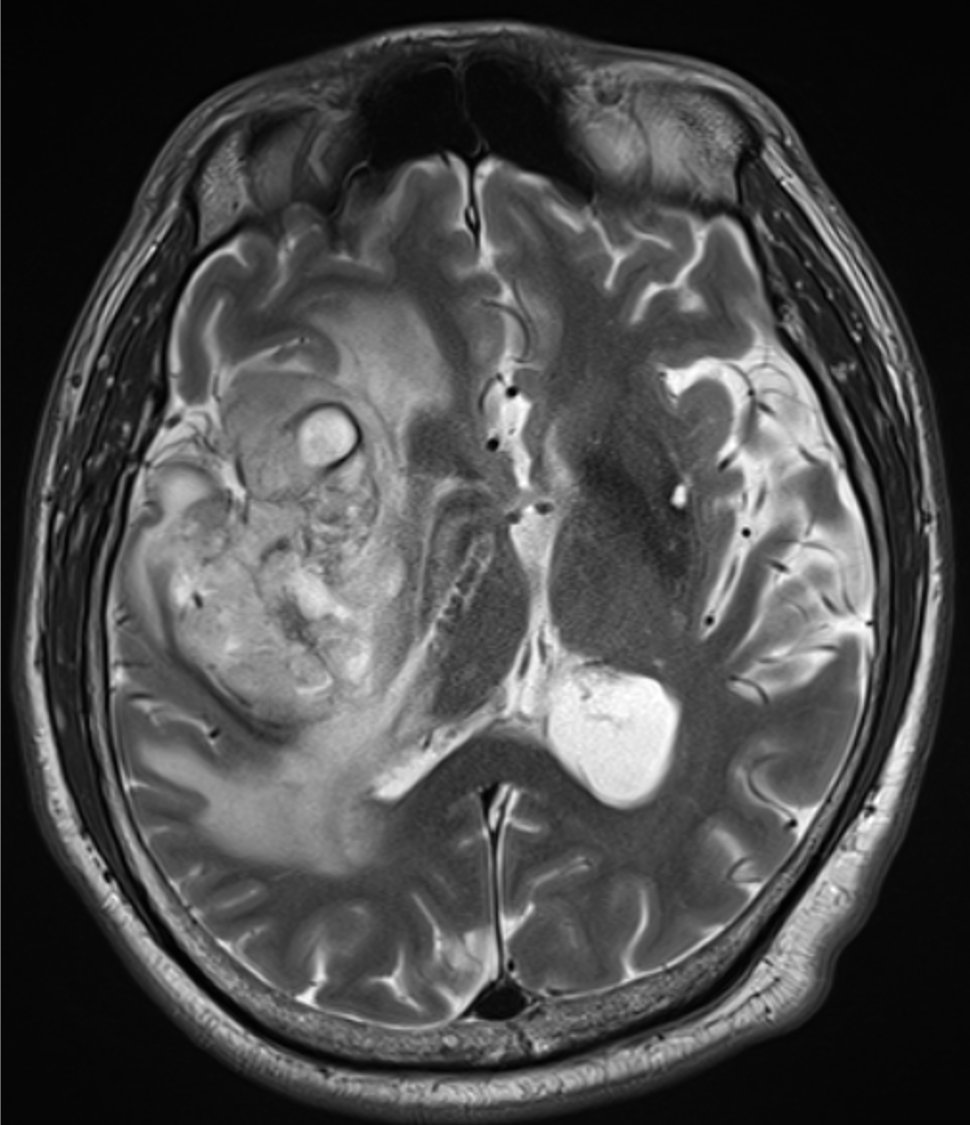

主訴は左下肢の脱力、歩行困難。右島回に5cm大の腫瘤を指摘され、膠芽腫が疑われた。術前の血管評価のため頭部CTA、CTVを施行した。

手術が施行され、glioblastoma, IDH-wild type, CNS WHO grade 4と診断された。現在、放射線化学療法中である。

当該疾患の診断における造影CTの役割

島回部のglioblastomaの術前CTAにおいて、手術中の予期せぬ血管損傷の回避、ひいては術中出血や虚血性合併症のリスク低減のために中大脳動脈や穿通枝など主要血管を可視化する必要がある。血管と腫瘍の位置関係を把握することで、腫瘍をできる限り摘出しつつも神経機能を温存する戦略を立てることができるようになる。隣接する基底核部は錐体路や感覚路と近接するため、摘出範囲の判断のために術前の血管情報が不可欠である。

また、術前の血管画像をナビゲーションシステムに統合することで、リアルタイムに血管・神経の位置を確認しながら手術が進められ、より手術の安全性を高めることができる。膠芽腫は浸潤性が強いため、血管を温存しながらも腫瘍を完全に摘出することが困難であることが多く、機能温存と腫瘍制御の最適なバランスのために術前の詳細な血管描出が重要となる。